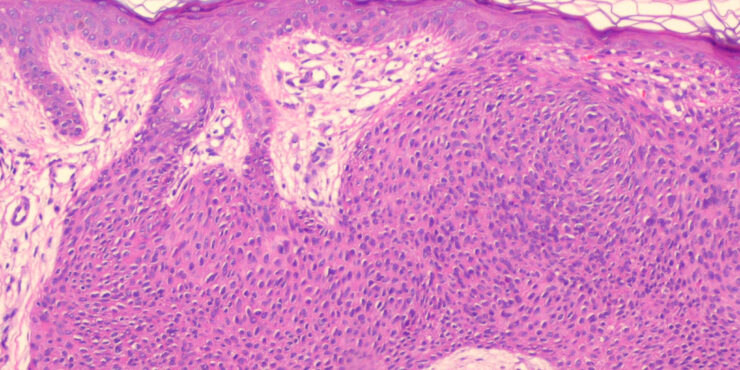

Herpes simplex = العقبول البسيط

Herpes simplex = العقبول البسيط OLYMPUS DIGITAL CAMERA OLYMPUS DIGITAL CAMERA OLYMPUS DIGITAL CAMERA OLYMPUS DIGITAL CAMERA OLYMPUS DIGITAL CAMERA OLYMPUS DIGITAL CAMERA OLYMPUS DIGITAL CAMERA OLYMPUS DIGITAL CAMERA OLYMPUS DIGITAL CAMERA